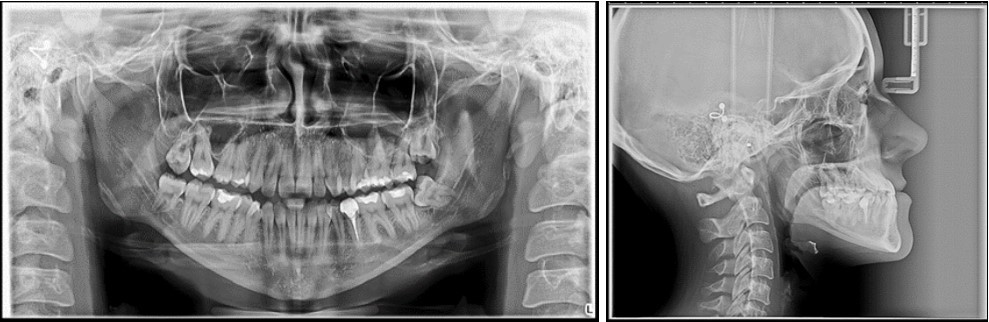

Post-surgical orthodontic treatment was started 4 weeks after the surgery. Wearing of bilateral box elastics was recommended in order to improve interdigitation. (Figure 6) The orthodontic treatment was finished on 0.019x0.025 SS archwires. Post-surgery cephalometric analysis revealed an increase in SNA value by 4 degrees (SNA 82 degrees) and a decrease in SNB value also by 4 degrees (SNB 79 degrees). The patient was now in a skeletal class I, with ANB 3 degrees. An examination of the soft tissue on the radiograph reveales a better relation between the upper and lower lip. (Figure 7).

Figure 6.Post-surgical intraoral photographs, with bilateral box elastics

Post-surgical intraoral photographs, with bilateral box elastics

Figure 7.Post-surgical panoramic and lateral cephalometric radiograph.

Post-surgical panoramic and lateral cephalometric radiograph.